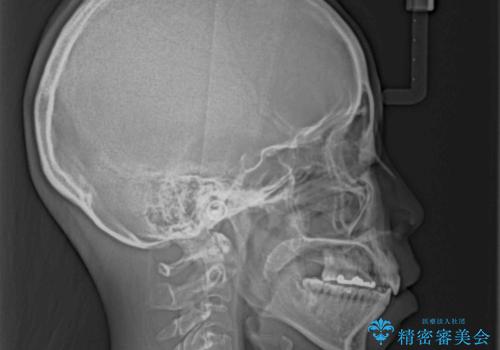

- 上の前歯の捻じれと突出感を気にして来院された患者様です。

目立たない装置を希望とのことで、上顎左右第一小臼歯を抜歯し、インビザラインにて矯正治療を行うこととしました。

インビザラインにて抜歯矯正を行うと、高頻度で奥歯が咬み合わなくなります。

抜歯スペースが閉じてからも咬みにくさ改善のためマウスピース矯正を継続するため、治療期間は長期化します。